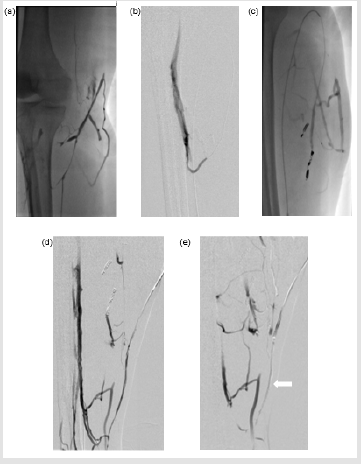

The principle of treatment was to obliterate the GSV using VCS followed by direct injection of sclerosant percutaneously into the superficial venous lesions. One of the reasons VCS was used to ablate the truncal vein was that one of the authors (TYT) has used the device successfully in recurrent GSV reflux post endothermal ablation on numerous occasions with no recanalization at 6 months on duplex ultrasound. The procedure was carried out under general anesthetic and antibiotic cover. The GSV was accessed using a micro puncture access system and Seldinger technique just above the medial malleolus and a second access point just above the knee joint. Venogram performed from the distal GSV access point revealed an abnormal dilated venous structure within the subcutaneous tissue of the medial aspect of the calf, which appeared to communicate with the GSV and draining into the deep venous system (Figure 2a & 2b). The deep veins were patent throughout. There was no evidence of filling of the small venous malformations, which were evident on the MRI. On table USS showed no obvious flow and was thought to be likely in keeping with thrombosis. Obliteration of the entire extent of the GSV from approximately 5 cm from the SFJ to the point of access above the medial malleolus was carried out using VCS as per instructions for use except that a double dose of glue was given initially to mitigate the chances of recurrence.

This was followed by accessing the superficial dilated tributary of the GSV within the calf from the most cranial access point using a microcatheter. The two areas of communication of this vessel with the deep veins were occluded using 2 mm x 14 cm micro coils (Figure 2c). Due to tortuosity, the actual large draining vein within the subcutaneous tissues of the calf could not be accessed by an endovascular approach. The vein was directly punctured percutaneously and was obliterated using STS foam (Figure 2d). A follow-up ultrasound scan (USS) performed 24 hours later showed thrombosis of the entire length of the GSV along and it is superficial tributary within the subcutaneous fat plane of the calf. No evidence of perfusion noted within the calf venous malformations (Figure 3). The deep veins of the right lower limb remained patent. The patient was given subcutaneous heparin to prevent deep vein thrombosis and oral NSAID for one week to attenuate the effect of thrombo-phlebitis and was subsequently discharged 24 hours later. Ultrasound follow up of the calf vm at 2 weeks and 3 months showed no flow within the venous anomaly and the GSV remained occluded to the ankle. The patient’s symptoms were much improved at the 2 follow-up time points and her lower leg varicosities had shrunken in size. Subjectively, she had experienced minimal postoperative pain (1/10) and no inflammation. Her rVCSS was 8 and 6 at 2 weeks and 3 months, respectively.

Figure 2: (a) The superficial GSV tributary which was seen communicating with the superficial venous malformation on MRI. (b) Communication with the deep venous system. (c) The two areas of communication with the deep veins were occluded using 2 mm x 14 cm microcoils. (d) Direct puncture of the superficial tributary of the GSV showing a patent superficial tributary of the GSV. (e) Post embolisation of the superficial tributary of the GSV using STS foam showing complete obliteration (arrow).